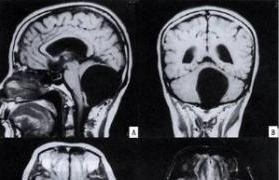

患者于3月前出现头晕症状,行走时向右侧倾斜,头痛头晕,自服“感冒药”后缓解。1周前头晕头痛加重,伴恶心、呕吐,为胃内容物,量约200ml,在医院行颅脑CT小脑蚓部低密度影,考虑占位性病变,建议性MR检查。为进一步诊治,故来我院行颅脑MRI检查提示小脑蚓部占位性病变,考虑囊肿,门诊以“小脑蚓部占位性病变(囊肿)”收住我科。发病以来神志清楚,精神差,饮食差、睡眠差,大小便正常,体重无明显变化,无抽搐,无咳血及血尿。

1. 颅脑CT平扫+增强示小脑蚓部低密度影,考虑占位性病变,建议MR检查。

2. 颅脑MR平扫+增强示颅脑MR平扫+增强示小脑蚓部异常信号影,考虑囊肿伴梗阻性脑积水。